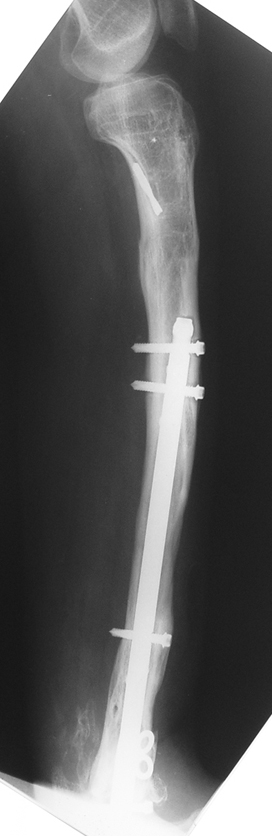

3. POSTTRAUMATIC LOWER LIMB SHORTNESS (MALUNION)

This type of shortness occurs after a fracture heals in a shortened position. Most cases are seen in adults and can be treated with one lengthening operation. Additional deformities can be corrected simultaneously. Most of these cases can be treated with lengthening over nail or just corrections and intramedullary nailing.